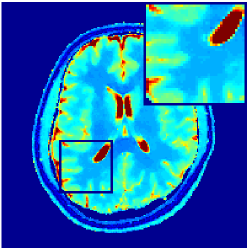

VI-E In-vivo experiments

Two sets of experiments were conducted here: first, we used the 2D and 3D acquisition sequences for scanning a healthy volunteer’s brain (real-world acquisitions). Figures 6 and 7 display the parametric maps reconstructed from 2D spiral and radial readouts. We computed the T1, T2 and proton density (PD) maps using baseline reconstruction algorithms ZF, VS, LR, FLOR, AIR-MRF and our proposed LRTV. While baselines use DM either for quantitative inference or also during reconstruction (i.e. AIR-MRF), we further compare the DM-free LRTV’s performance when cascaded to DM, KM and MRFResnet for quantitative inference. For the 3D spiral acquisitions we compared LRTV and its closest competitor VS in Figure 8. Outcomes from other tested algorithm are displayed in the supplementary materials (Figure S5). Since FLOR does not use dimensionality-reduction, our system ran out of memory during 3D reconstruction; hence results are not reported in this case.

VI-E1 Discussion

The LRTV-DM and LRTV-MRFResnet perform on par, and both outperform all tested baselines for reconstructing T1, T2 and PD maps in all acquisition schemes. This can be observed both visually in Figures 6, 7, 8, S2 and S3, and quantitatively in Table IV across all tested metrics. Other baselines were unable to successfully remove the under-sampling artefacts in TSMIs, and these errors propagated to the parameter inference phase and resulted in inaccurate maps. Temporal-only priors incorporated within LR are shown insufficient to regularise the inverse problem and LR sometimes (e.g. 2D spiral acquisitions) can admit solutions with even stronger artefacts than the model-free ZF baseline. This issue was previously studied for other non-Cartesian MRF readouts that similar to our spiral/radial trajectories, miss to sample the corners of the k-space in all timeframes (see section 2.2.2 and figure 2 in [19]). In the absence of reference for the k-space corners information, the LR iterations despite minimising the objective can converge to solutions with high-frequency artefacts, as visible in the computed maps. This highlights the need for adding an appropriate spatial-domain regularisation. FLOR reduces the LR’s artefacts but this improvement is limited because the suggested nuclear norm penalty does not incorporate an explicit spatial regularisation. Further for reducing artefacts, FLOR can introduce an undesirable bias in the computed T1/T2 maps e.g. see error maps in Figures S2 and S3. The non model-based VS baseline incorporates spatial regularisation and results in spatially smoother maps than ZF and LR, but it is unable to output artefact-free images. Further and consistent with our in-vitro experiment, we observe that VS overestimates the T2 values (e.g. in White and Grey matter regions) in tested 2D acquisitions i.e. the spatial regularisation trades off agains the quantification accuracy. The model-based AIR-MRF adds spatial regularisation through 2D/3D low-pass Gaussian filters however this trades off the sharpness of the computed maps and can increase the errors at the tissue boundaries (we searched Gaussian spreads that keep the blurs and high-frequency artefacts minimal). For our acquisition readouts, Gaussian filters performed better than disk filters of [19] for avoiding strong Gibbs artefacts. On the other hand, the spatiotemporally regularised LRTV greatly improves the TSMI reconstructions i.e. 4 dB enhancement compared to the closest competitor baseline (Table IV). This enables computing accurate and aliased-free multi-parametric inference using DM or the DM-free learning-based alternative MRFResnet as visible in Figures 6, 7, 8, S2 and S3. MRResnet and DM score competitive quantitative inference results i.e. T1 and T2 MAPE less than 5% and 9%, respectively (Table IV). KM also outputs comparably accurate T1 maps, however this shallow learning model despite having a model size larger than MRFResnet, is unable to learn accurate T2/PD quantification and it results in poor estimated maps, consistent with our observations in section VI-C.